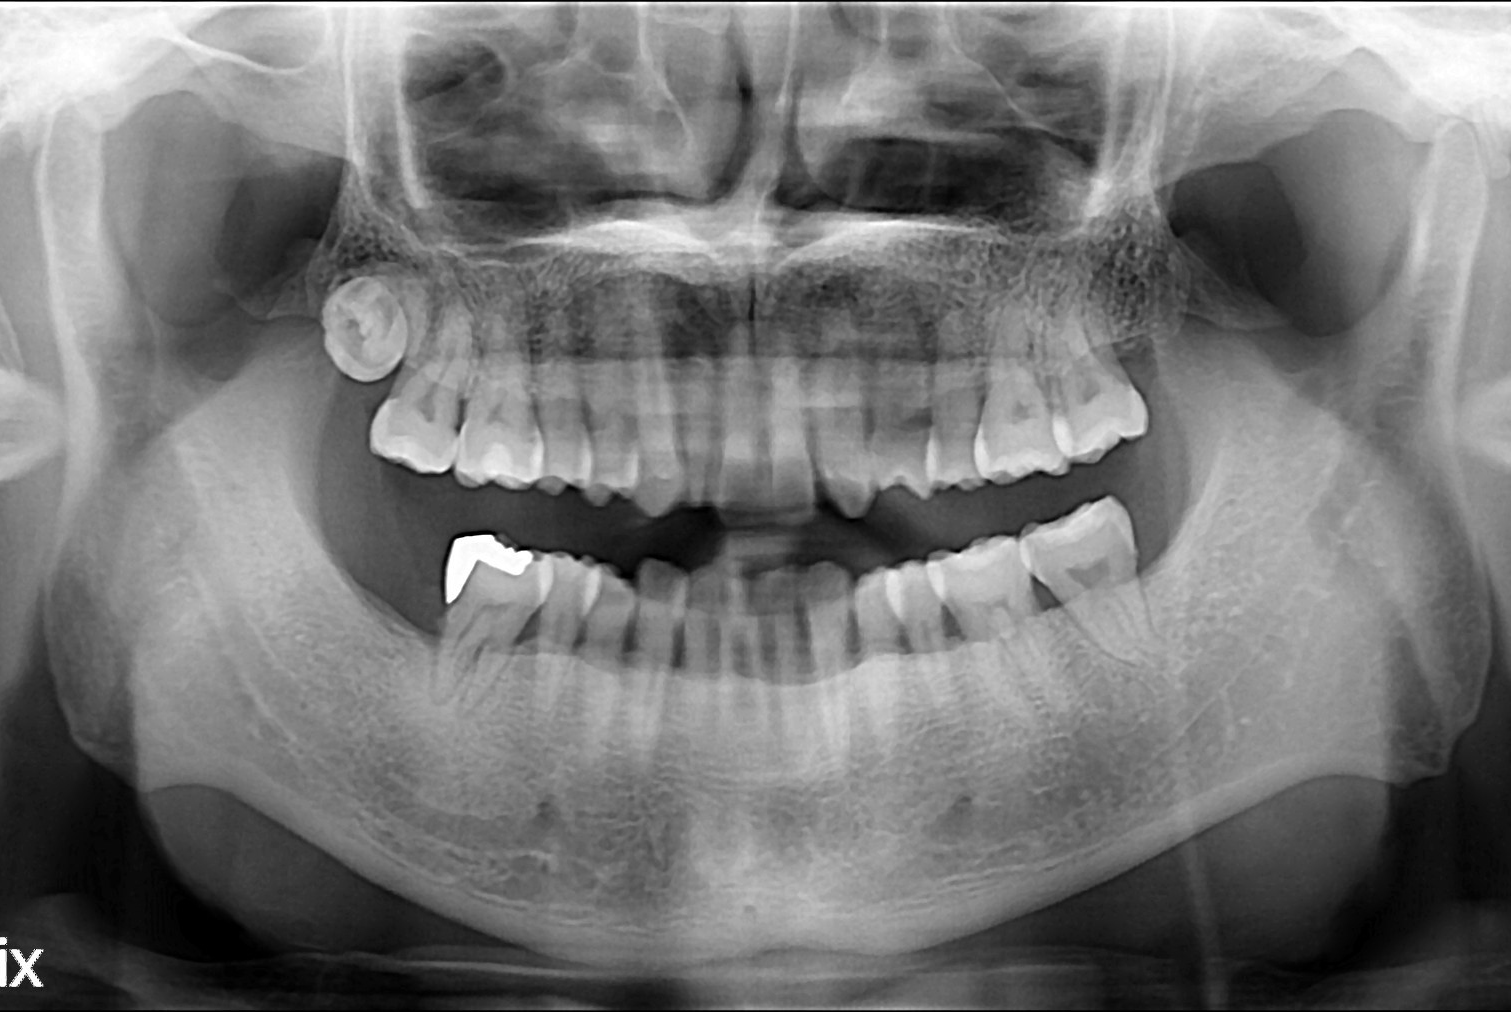

치료전 : 2017-10-19

세종치과는 많은 환자와 다양한 케이스를 바탕으로 항상 편안한 임플란트 수술을 제공하고자 노력하고,

오래동안 튼튼히 쓸 수 있는 임플란트 수술을 가장 큰 목표로 삼고 있습니다